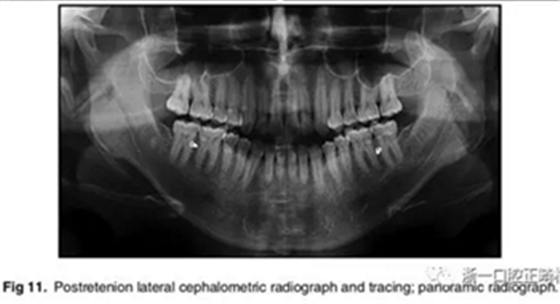

影像學:全景片示:牙根平行度可。頭顱側位片及疊加圖示:下頜骨發(fā)生逆時針旋轉,面部輪廓改善;上切牙轉矩正常,下切牙輕微舌傾;唇突度減小,鼻唇角增大。